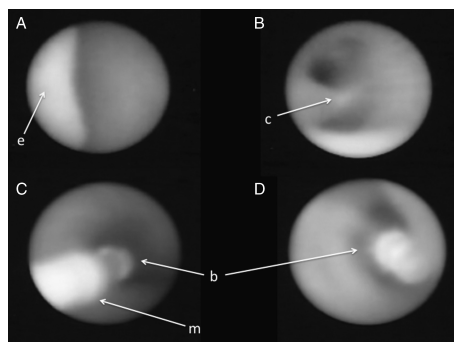

Рисунок 3 | Техника баллонной окклюзии трахеи на 26 неделе гестации. А — надгортанник плода (е), В — бифуркация трахеи (с), С — баллон (b) c микрокатетером (m), D — баллон (b) после раскрытия.

Вмешательство предпочтительно проводить между 26–30 неделями гестации, т. к. введение баллона раньше этого срока может повлечь за собой повреждение трахеи. Фетоскоп вводится в амниотическую полость и подводится ко рту плода, избегая плаценты. Далее его вводят в ротовую полость и продвигаются вдоль гортани, трахеи до бифуркации, после чего баллон раздувается с помощью введения 0,8 мл физиологического раствора. После того как врач убедится в правильной позиции баллона посредством фетоскопии или УЗИ, устройство отсоединяется от микрокатетера. После оценки состояния плода и матери фетоскоп извлекается, и процедура считается завершенной. Беременная женщина находится под наблюдением в стационаре первые 24–48 часов с непрерывным мониторингом состояния плода, далее контроль состояния плода и положения баллона производится каждые две недели до родов.

Удаление баллона производится на 34 неделе с помощью повторной фетоскопии или прокола баллона под контролем УЗИ.